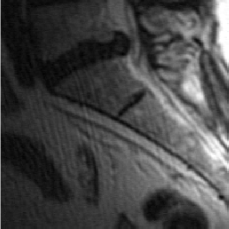

Figure 2: Test Images.

We turn now to test TDIHT for high dimensional signals. We test the performance of several MRI images: the Shepp-Logan phantom, FLAIT brain image, T2 Sagittal view of the lumbar spine and the circle of Willis. The first image is of size 256×256256256256\times 256, while the other are of size 512×512512512512\times 512. They are all presented in Fig. 2.